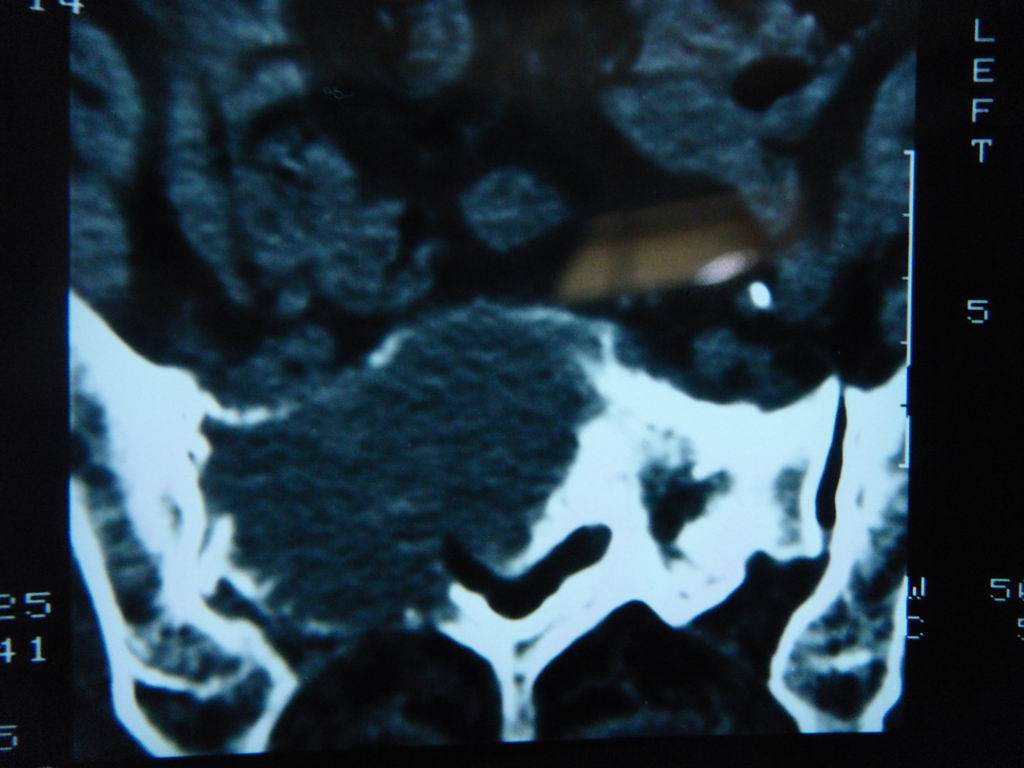

标题: CT21430:女性65岁 乳腺癌术后3年 [打印本页]

标题: CT21430:女性65岁 乳腺癌术后3年

结合病史,考虑骶骨转移瘤,但软组织肿块未突破骨壳,骨巨细胞瘤不能完全排除,骨髓瘤及脊索瘤不考虑。

结合病史,考虑骶骨转移瘤。

结合病史,考虑骶骨转移瘤。其它椎体,如腰5是否有问题呢?

个人感觉骨巨细胞瘤可能性大些。